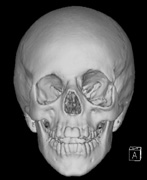

CNS hemangiomas are the most common tumor of VHL, affecting 60% to 80%, with a predilection for the cerebellum and spinal chord. An enlarging cystic component is a frequent finding in symptomatic tumors. Patients typically present in their early 30s; headaches or neck pain in affected individuals should not be ignored.172,173 On microscopy, CNS hemangiomas resemble retinal capillary hemangiomas. Their malignant potential is low.174 The treatment is surgical (Fig. 17, A and B).13

Fig. 17. Images from a 13-year-old boy with Von Hippel-Lindau syndrome. (a) Coronal postcontrast T1-weighted imaging reveals a cystic lesion with an enhancing nodule at the pial surface typical of a hemangioblastoma. (b) A second solid enhancing hemangioblastoma is seen at the craniocervial junction on a sagittal postcontrast T1-weighted image. (c) Associated cystic lesions (arrows) are seen within the pancreas.